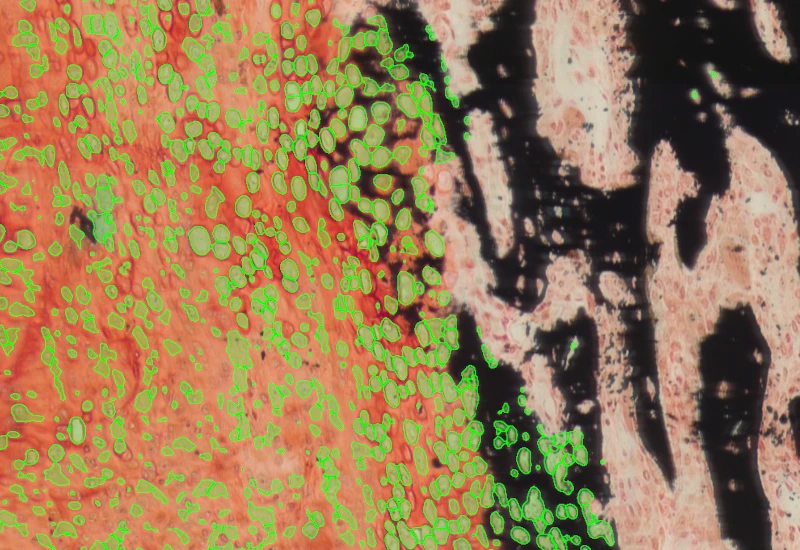

TissueGnostics provides advanced solutions for whole-slide imaging and image analysis in biological and clinical research. Our products help researchers to scan and analyze complex tissue samples, enabling more detailed insights into tissue structure, cellular interactions, and spatial cell landscape.